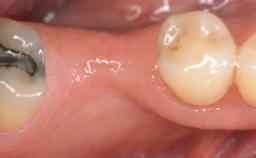

It is sometimes necessary to remove and replace compromised implants. This case is a clear example of the need for multiple steps to achieve an optimal therapeutic result for patients with non-salvageable implants. It illustrates how the lost soft and hard tissues were rebuilt in a sequence that improved the healing of the hard tissues and assured their long-term stability. The 35-year-old healthy patient presented with clinical attachment loss on the proximal and lingual surfaces of the natural dentition. Some gingival recession was present on natural teeth, particularly in the posterior sextants (S1, S3, S4, and S6).

Area Anterior|Posterior

Bone Augmentation Horizontal|Staged|Vertical

Augmentation Materials Autogenous chips|Autogenous block(s)|Xenogenous